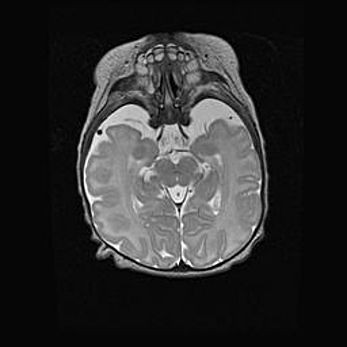

Сообщающаяся гидроцефалия. Кистозная энцефаломаляция головного мозга.

Возраст: 3 месяца 4 дня

Вес: 3100 г

Пол: женский

Окружность головы: 34 см

Срок гестации: 31 неделя

Кистозная энцефаломаляция головного мозга - одна из форм поражения головного мозга в детском возрасте. Характеризуется возникновением множественных и распространённых кист в коре, белом веществе и подкорковых образованиях головного мозга у плодов, новорождённых и детей раннего возраста. Развитие кистозной энцефаломаляции связано с внутриутробной асфиксией и гипотонией, родовой травмой, тромбозом синусов, пороками развития сосудов, инфекциями, сепсисом и другими причинами. Наиболее значимые инфекционные агенты: вирусы простого герпеса, цитомегалии, краснухи, токсоплазмы, энтеробактерии, золотистый стафилококк и другие.